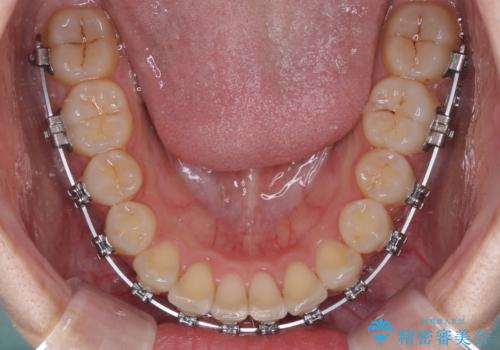

- 矯正装置

- メタルブラケット

- 上下前歯のデコボコを気にして来院された患者様です。

ワイヤー矯正でもインビザラインでも、どの装置でも対応可能でしたが、安価で楽して素早く治療を終えたいとのことで、メタルブラケット装置による矯正治療を行うこととしました。

治療中は大きなトラブルもなく、予定の1年半でスムーズに治療を終えることができました。